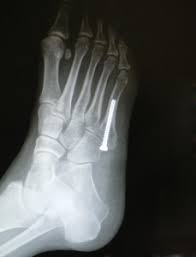

The sutures in the small incision will need to be removed after 10 to 14 days. See more ideas about fracture healing, jones fracture, fracture. These are notorious for very slow healing. What is the recovery time of a broken ankle? Do you have a jones fracture of the 5th metatarsal? Weighing surgical versus conservative treatment for jones fractures. Well find out exactly how to get this bone feeling better! This is an ap view of a percutaneous jones fracture surgery. Outside of the foot pain can be improved with a few simple treatment. While people can relate to a stubbed toe or sprained ankle; Surgical treatment of femoral neck fracture. 5th metatarsal fracture recovery time: A jones fracture occurs in a region known as the the incision required to repair a jones fracture is small and the surgery can be done as an outpatient procedure under general or local anesthesia.

Intramedullary Screw Fixation Of Proximal Fifth Metatarsal Fractures In Athletes from www.scielo.br Lengthy healing times and risk of refracture may be reasons for surgical repair in these fractures. A foot can be broken in many places learn about the jones fracture, what types of treatments are available, and if jones fracture surgery is the best treatment option. Patient may be in a removable boot after surgery for a week or two at the direction of the physician. Jones fractures are named after sir robert jonestrusted source , an orthopedic surgeon who in 1902 reported on his own injury and the injuries of several people he. Do you have a jones fracture of the 5th metatarsal? Jones fracture surgery recovery on mainkeys. A jones fracture is a break between the base and middle part of the fifth metatarsal of the foot. Yet surgery is not always necessary.